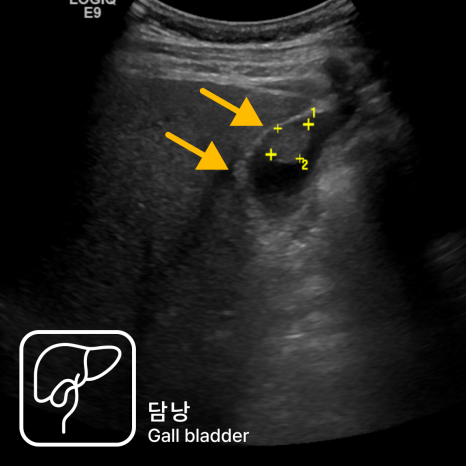

식도: 역류성 식도염·바렛 식도

식도 하부가 붉게 헐어 있거나 줄무늬 모양의 미란이 보이면 역류성 식도염으로 진단할 수 있습니다. 만성적으로 위산이 올라온 경우 식도 상피가 변하는 바렛 식도가 발견되기도 하며, 이 경우 정기적인 추적 내시경이 필요합니다.

위: 위염·위궤양·용종

위 점막이 붉고 부어 있거나 미세한 출혈점이 보이면 위염, 깊게 패인 병변이 있으면 위궤양을 의심합니다. 돌출된 용종이 보이는 경우 크기와 모양에 따라 조직검사 또는 내시경 절제를 시행해 양성/악성 여부를 확인합니다.